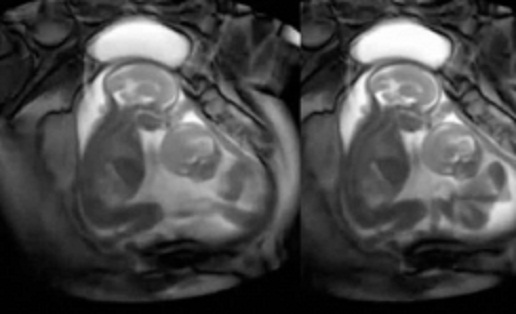

தாயின் கருவறையில் இருக்கும் இரட்டை சுசுக்கள், கருவில் வளரும் போதே ஒருவரை ஒருவர் அடித்து உதைத்து விளையாடி கொண்டிருப்பது போன்று காட்சிகள் கொண்டிருக்கிறது இந்த காணொளிப்பதிவு.

இந்த காணொளிப்பதிவில் இரட்டையர்கள் இருவர் அடித்து விளையாடுவது. ஒருவரை ஒருவர் மாறி, மாறி அடிக்க முயல்வது மிக தத்ரூபமாக இருக்கிறது. பிறந்த பிறகு அல்ல, கருவறையிலேயே நாங்கள் எங்கள் சுட்டித்தனத்தை துவங்கிவிட்டோம் என கூறுவது போல இருக்கிறது இந்த காணொளி.

இந்த காணொளிப்பதிவு உண்மையாகவே ஸ்கேனிங்கின் போது பதிவு செய்யப்பட்டதா? அல்ல கிராபிக்ஸ் உதவியால் உருவாக்கப்பட்டதா? என்ற கேள்விகள் மனதில் எழுந்தாலும். கருவில் வளரும் இரட்டையர்கள் ஒருவருடன் ஒருவர் விளையாடுவது உண்மையே என்கிறது அறிவியல்.